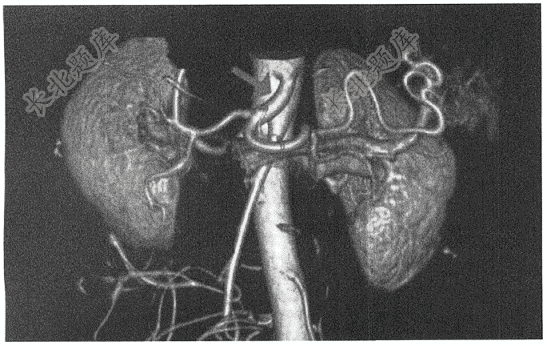

- 单项选择题此动脉CTA中箭头所示为( )

A、腹腔干

B、肝固有动脉

C、肠系膜下动脉

D、肠系膜上动脉

E、胃左动脉